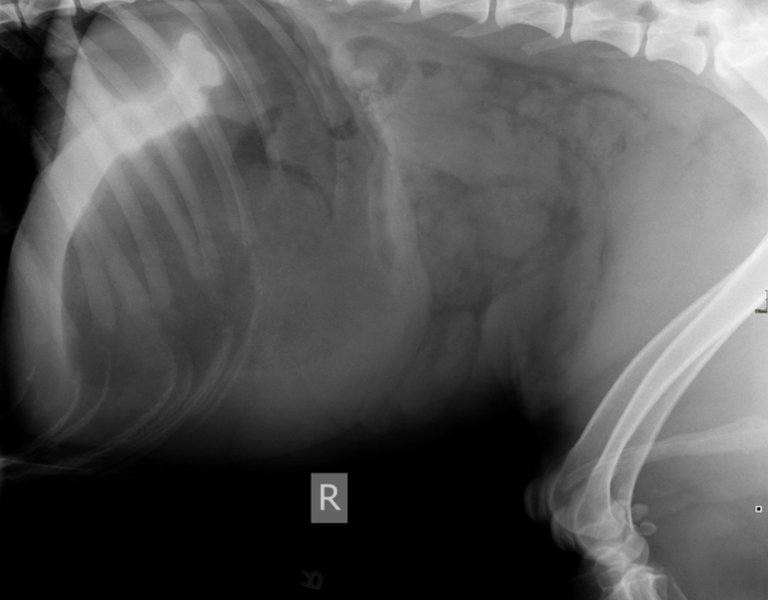

Radiographs, preferably a right lateral image were performed by the referring hospital. Koda’s images were interpreted by IVS’s Dr. Hoyt, and revealed a classic gas pattern referred to as “Popeye’s arm”. Bloodwork, including a complete

blood count, chemistry and electrolyte panel, lactate, and a PT/PTT all had values within the normal reference interval.